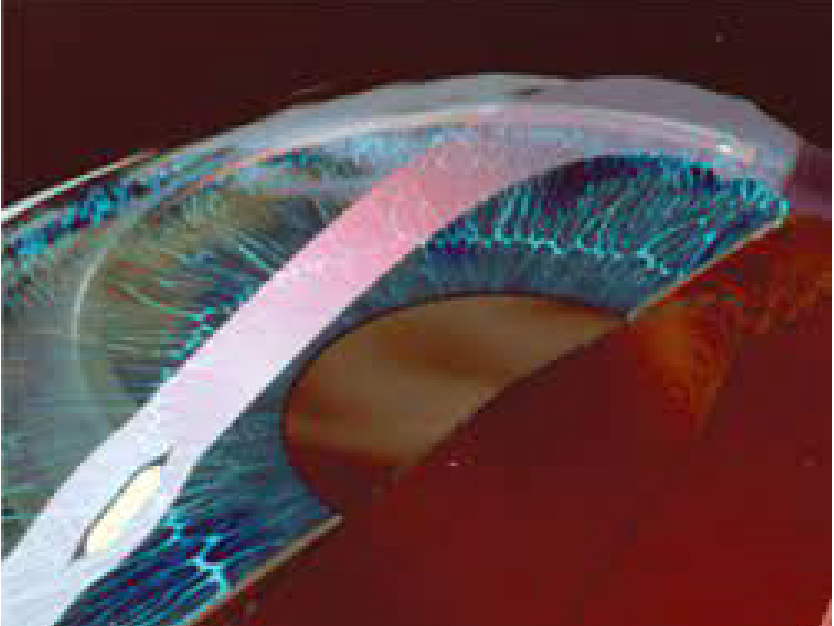

Corneal Transplantation

Parker Cornea specialists are experts at a wide array of corneal transplantation procedures, including DSAEK, DMEK, DWEK/DSO; Anterior lamellar keratoplasty, Penetrating keratoplasty and Boston Keratoprosthesis.